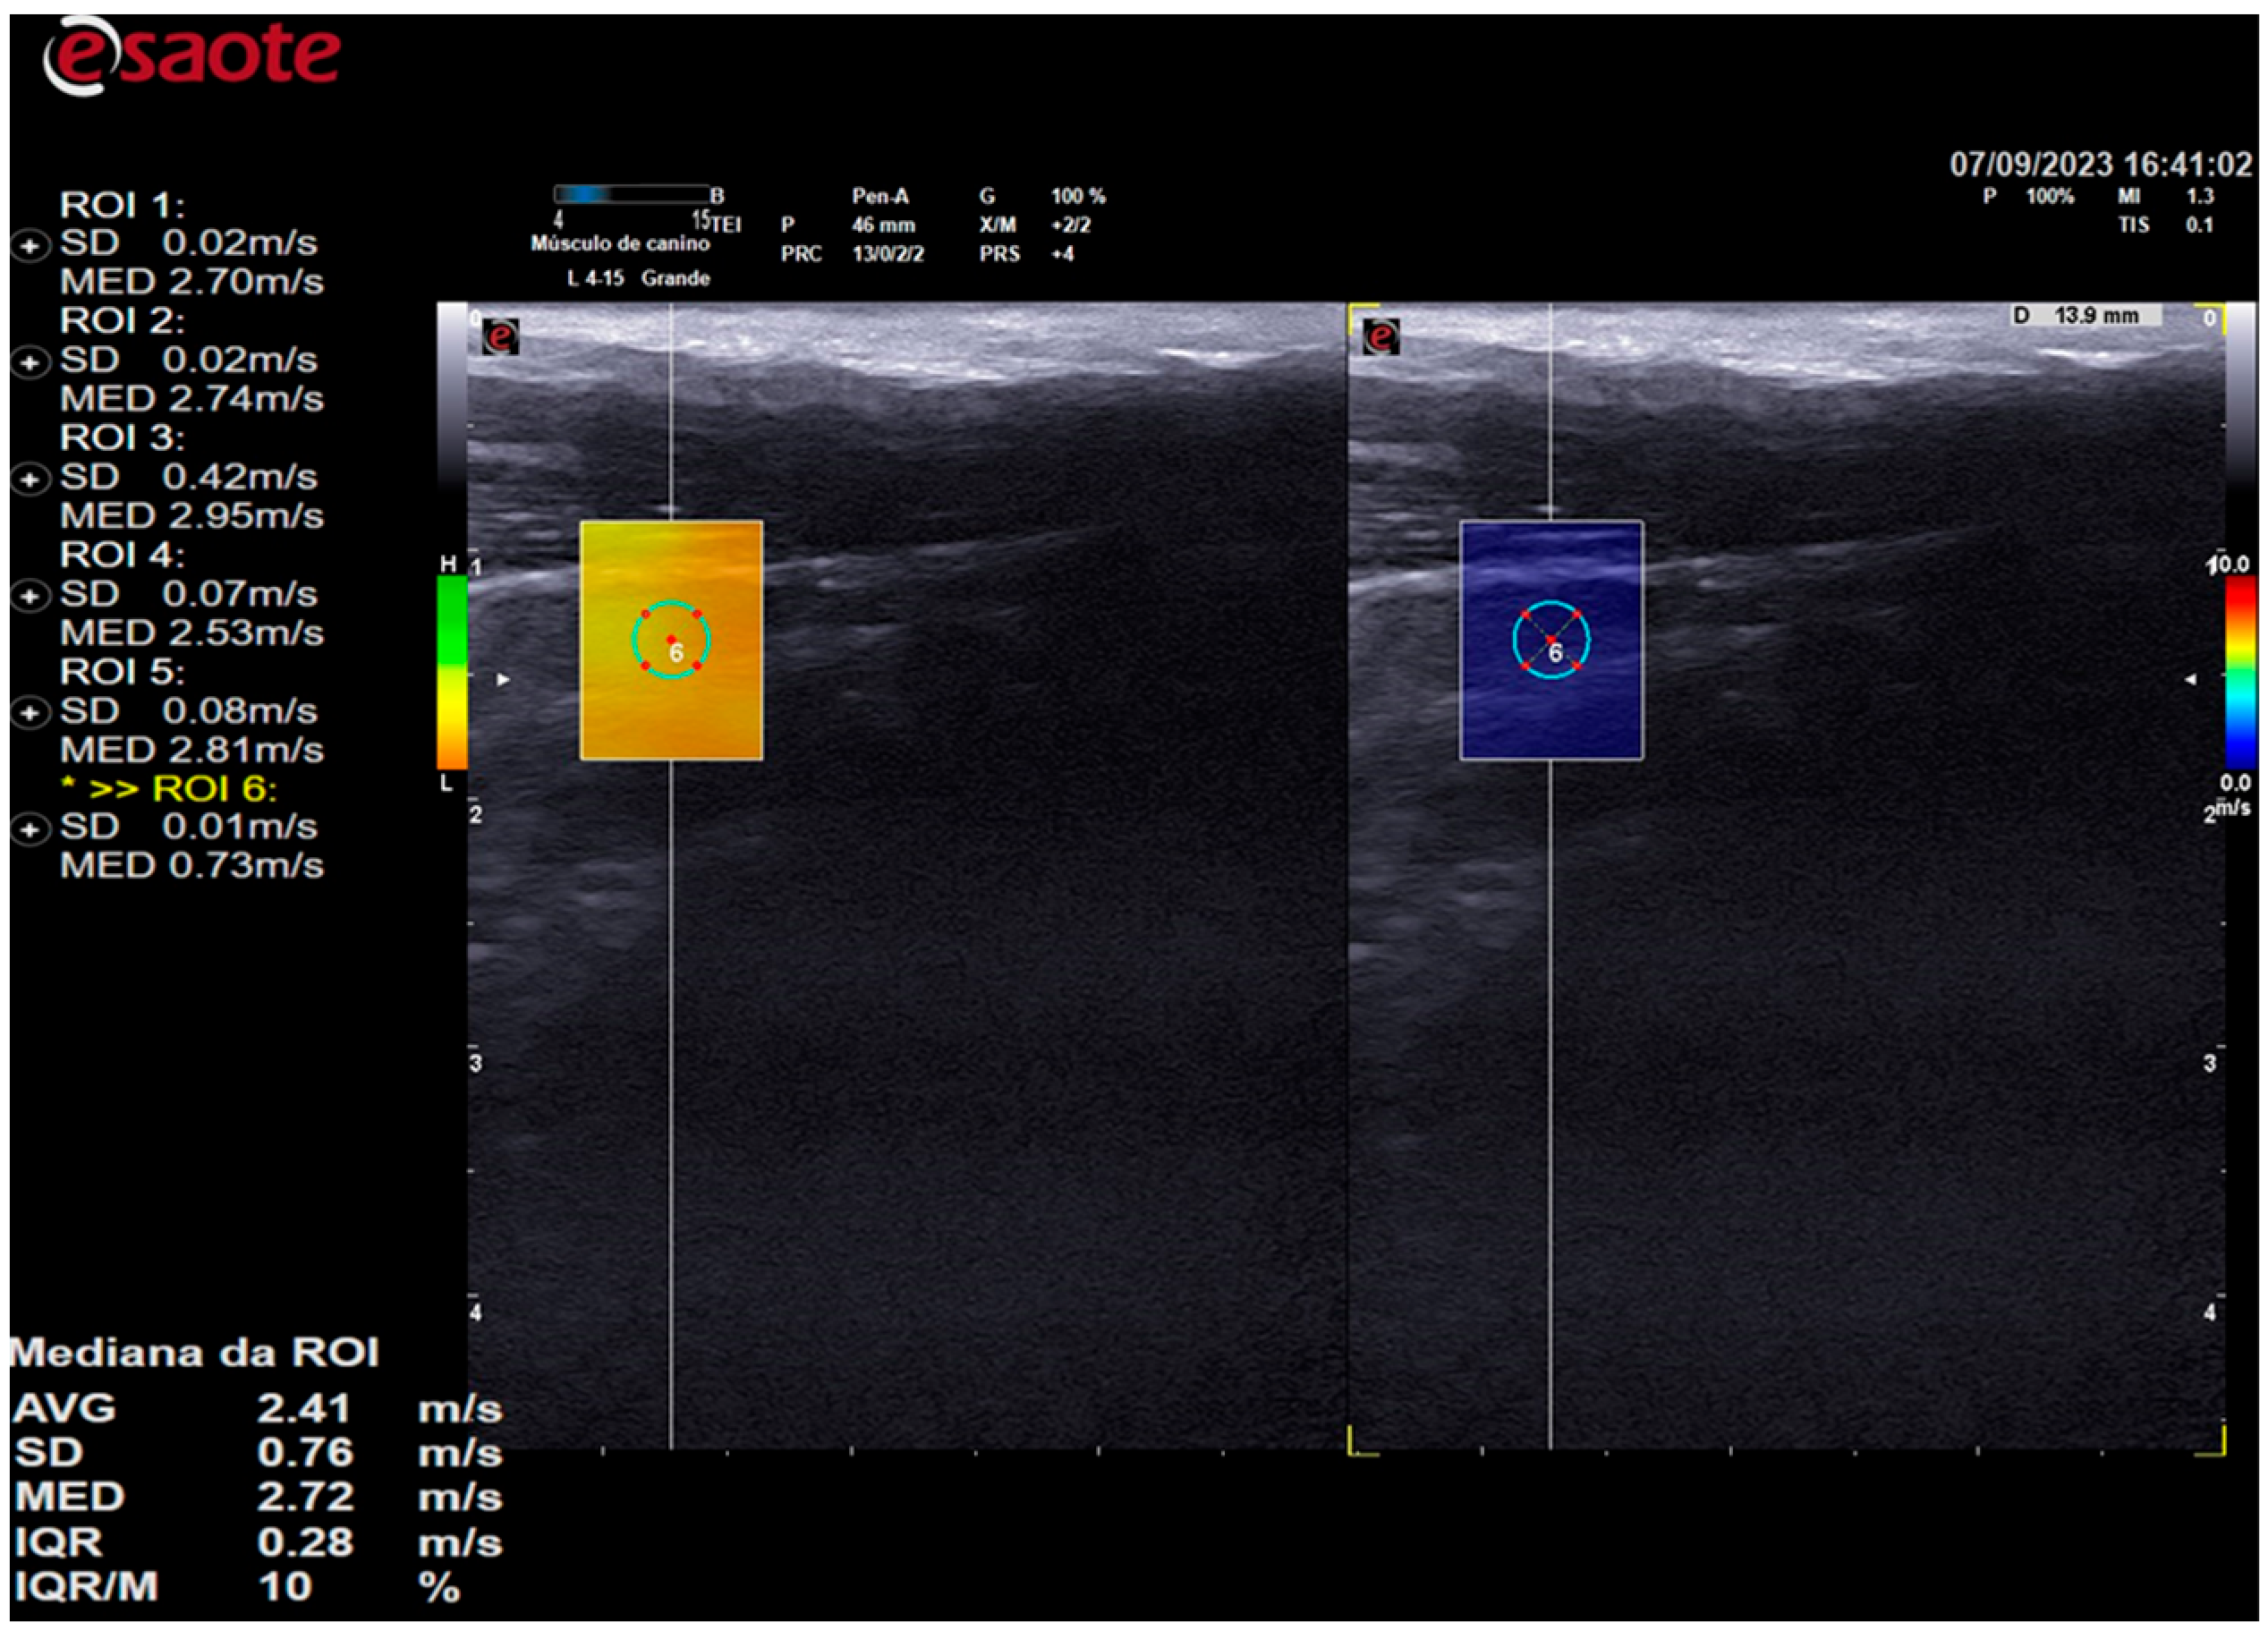

Elastographic images were obtained in the longitudinal plane of each thyroid lobe, and a scale of 0.0 to 10.0 m/s was employed in all cases. Once the thyroid lobe was properly framed in the image, the QelaXtoTM 2D software quality map was initiated. The map indicated the most suitable locations for acquiring shear-wave velocity. These were colored green to indicate high quality (Figure 3), yellow to indicate medium quality, and orange to indicate low quality (Figure 4).

Figure 3. The image on the left is a 2D shear-wave elastography image of the left thyroid lobe of a 10-year-old dog. The elastographic image on the left shows a quality map from the QelaXtoTM 2D software, which is colored green. This indicates that the image is of high quality for measuring shear-wave velocity, which is a quantitative measurement. The right side of the elastographic image displays the colored elastogram (qualitative) from the QelaXtoTM 2D software in blue, indicating that the thyroid parenchyma had low stiffness (soft).